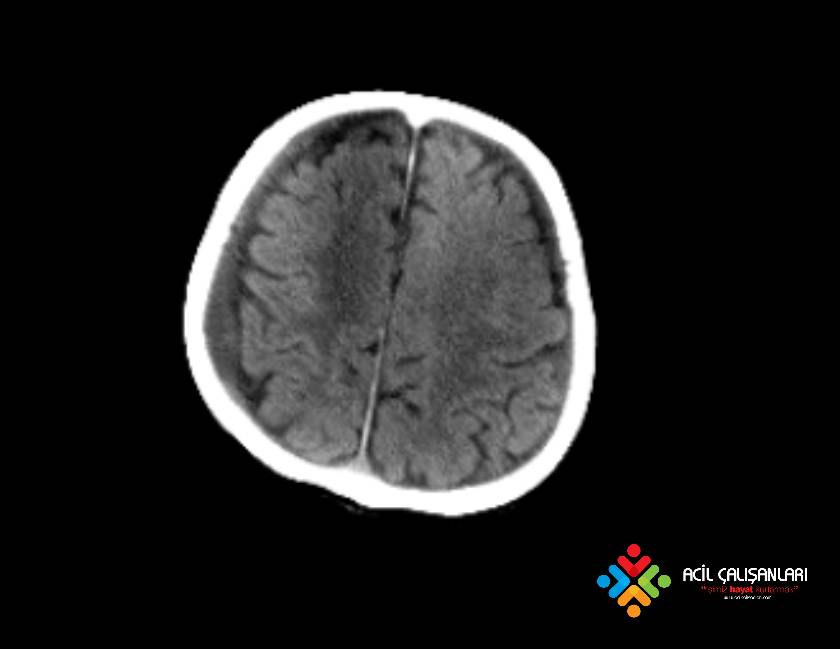

65 yaşında erkek hasta, bilinç değişikliği, saçmalama şikayeti ile acil servise başvuruyor. Hastanın öyküsünde bakıcısı ile kaldığı, birkaç gündür hareketlerine anormallik olduğu, ara ara saçmaladığı öğreniliyor. Hasta acil hekimi tarafından değerlendirildiğinde; GKS:15 Nabız: 92 atım/dk düzenli ; Solunum sayısı: 16/dk ; SpO2: 96 ; KŞ: 110 ve Kan Basıncı: 110/60 mm/Hg olarak değerlendiriliyor. Fizik mueyenede nöromotor sağlam, diğer sistemler normal olarak saptanıyor. Acil hekimi aşağıda görüldüğü gibi hastanın beyin tomografisini çekiyor. Bundan sonraki tanı ve yaklaşım ne olmalıdır?

Subdural hematom, beynin yüzeyinde, duramater adı verilen koruyucu zarın hemen altında meydana gelen hemrajidir. Subdural kanamada, kanama genellikle venlerden kaynaklanır ve yavaş ilerler, dolayısıyla belirtilerin ortaya çıkması bazen günler hatta haftalar alabilir. Subdural hematomlar, dura ve araknoid membranlar arasında subdural aralıkta, köprü venlerinin yırtılması sonucu gelişen ve radyolojik olarak konkav (yarım ay) şeklindeki kanamalardır. Bazen %20-30 vakada arteryel rüptürden de kaynaklanabilir. Kanama genellikle venlerden kaynaklanadığı için klinik yavaş ilerler, dolayısıyla belirtilerin ortaya çıkması bazen günler hatta haftalar alabilir. Subdural hematom genellikle yaşlılarda görülür. Gençlerde nadir görünen subdural hematom çoğu zaman travma sebebiyle oluşur. Subdural hematom yaşlılarda ve erkeklerde daha fazla görülmektedir. Etiyolojiye bakıldığında trafik kazaları ve düşmeler en sık sebebi oluşturmakta olup diğer nedenler arasında ateşli silah yaralanması, darp ve spontan kanamalar yer almaktadır. Özellikle ağır kafa travmalı olgularda görülme insidensi %30’dur. Subdural hematom travmadan itibaren hematomun ortaya çıkma süresine göre akut, subakut ve kronik olarak sınıflandırılmaktadır.

- Akut: 3 güne kadar

- Subakut: 4 gün ile 20 gün arası

- Kronik: 21 gün ve üzeri